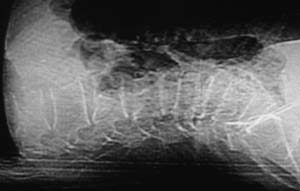

以下是引用余辉在2008-4-27 17:12:00的发言:[br]骨质疏松伴病理性压缩性骨折,椎骨骨松质密度减低,椎体骨小梁稀疏且普遍呈火柴头样改变,椎体无膨胀,无软组织肿块

以下是引用mzh123在2008-4-27 19:33:00的发言:[br]除压缩骨折表现外 还有许莫氏结节改变

以下是引用随光逐影在2008-4-27 21:29:00的发言:[br]除压缩性骨折外,还有许莫氏结节及骨质疏松表现。